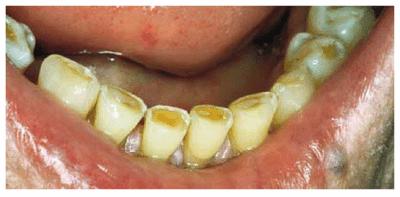

Figures 29-12A to C show a 75-year-old woman who presented

with severe root caries and moderate periodontal disease. Her daughter, who

disclosed that her mother was difficult to please, referred her. The daughter

was very supportive of her mother receiving dental treatment; however, her

mother was initially not interested. The mother did not think that the esthetic

aspect of dentistry was important. During consultation with the dentist, the

mother was informed of the infection in her mouth and the potential effect that

this could have on her future health and functionality. The patient consented

to have the maxillary arch restored with fixed prosthodontics. She refused to

accept treatment for her mandibular teeth, preferring to use her existing

partial denture. Figures 29-12D, and 29-12E show the final result after periodontal and

prosthodontic treatment. Although the patient was not particularly grateful to

have the dental treatment, her family was thrilled to have the caries infection

removed and the esthetic appearance improved. The patient lived with her

esthetically improved appearance for an additional 13 years.

Figure 29-12A to C: This 75-year-old woman had severe root caries and moderate periodontal disease.

Figure 29-12D: Although this woman stated that she would "just as soon have her teeth extracted," she was motivated to have both periodontal and prosthodontic treatment.

Figure 29-12E: The patient's smile after esthetic dental treatment shows just how much she appreciated her dental treatment.